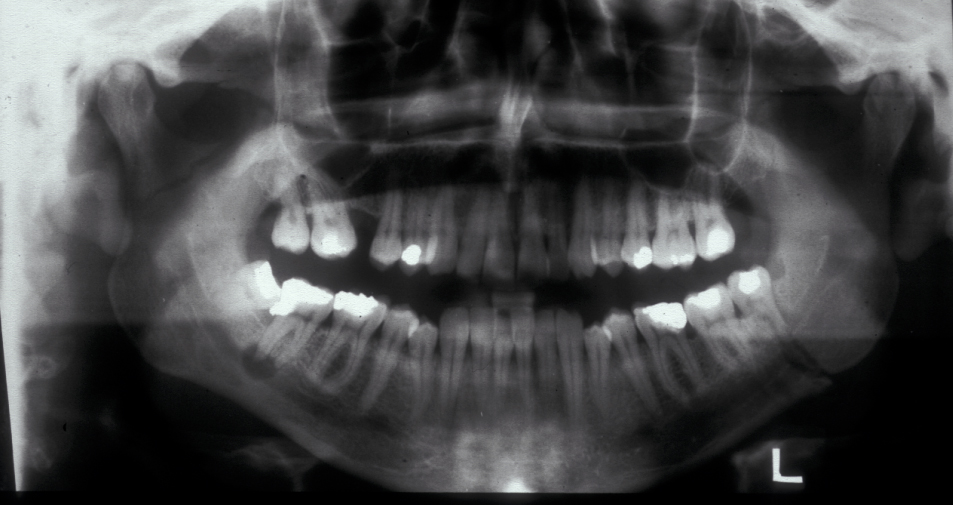

Figure 2 and Figure 3 illustrate examples of indications for removal of a third molar tooth.

Assessment of the tooth is both clinical and radiographic. If somebody presents in pain, it is important to establish that this is coming from the third molar and not elsewhere. Pain is often vague, poorly localised and may be referred from another tooth, or as part of facial arthromyalgia (condition affecting the jaw joint). A dental panoramic radiograph is ideal as it helps to assess all the teeth at once. The health of the adjacent molars may influence the decision whether to remove the third molar or not. Large crowns or old restorations are all at risk of dislodgement during surgery. It is also worth considering whether alternative treatment options are available. For instance, pericoronitis due to an over-erupted upper third molar may be dealt with by extracting that tooth only, with or without operculectomy. In the presence of other teeth of poor prognosis, will it be better in the long term to save the third molar which may be used as a denture or bridge abutment in the future?

These points help to determine whether the tooth can be simply elevated or will need a surgical approach. A series of radiographs depicted in Figure 4 to Figure 8 illustrate these points further.